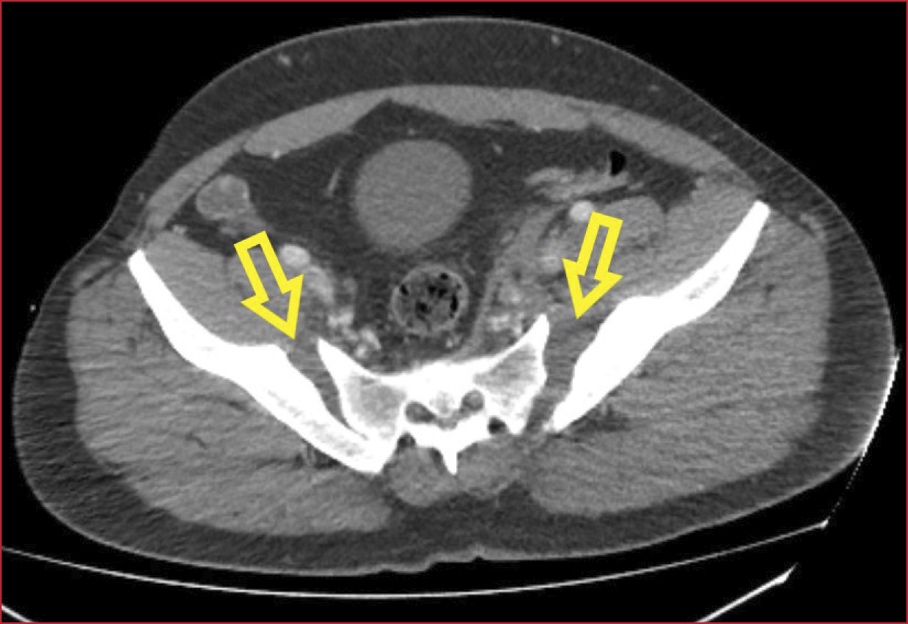

Hombre de 43 años, sin antecedentes personales de interés, que ingresa en nuestra Unidad, tras sufrir un traumatismo pélvico repetitivo con el cuerno o la perilla de la montura en la doma de caballo. El paciente es trasladado al Servicio de Urgencias hospitalario con incapacidad para deambular y dolor intenso. Se realiza una tomografía computarizada abdomino-pélvica de urgencia, que muestra una fractura inestable de pelvis tipo C2 de la clasificación de Tile, en libro abierto, con diástasis de la sínfisis púbica de 9,5 cm (Figura 1, flecha), articulación sacroilíaca izquierda y derecha (Figura 2, flechas), asociada con hematoma de partes blandas en el pubis y la región ilíaca izquierda, y sangrado activo en dicha zona. Se procede a la fijación externa urgente a cargo del equipo de guardia de Traumatología y se lo traslada a la Unidad de Cuidados Intensivos, donde posteriormente es sometido a fijación y osteosíntesis del anillo pélvico (Figura 3, flecha).

Figura 2. Tomografía computarizada de pelvis, corte axial. Diástasis de ambas articulaciones sacroilíacas.